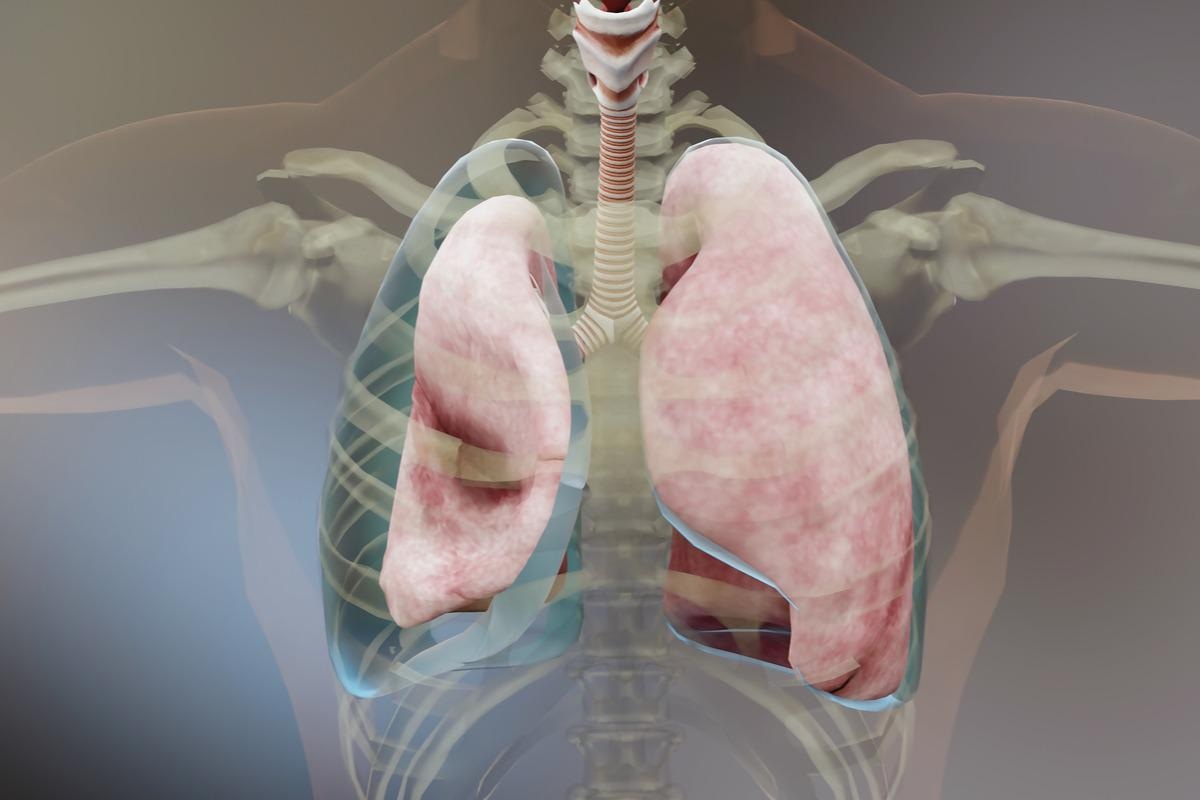

Empyema is a medical term used for pus pockets that have accumulated inside a body cavity, for example, pleural space. This condition occurs when a bacterial infection remains untreated or if it does not respond completely to treatment.

Empyema is a severe condition that necessitates medical attention. It can cause chest pains, coughing up mucus, fever, and shortness of breath.

Image Credit: ALIOUI MA/Shutterstock

A pleura is a smooth layer that covers the interiors of the chest cavity and lungs. A thin space known as pleural space is filled with pleural fluid that separates these layers, which are almost in contact. This fluid sometimes accumulates and becomes infectious, and the collection of pus begins, which thickens and leads to the sticking of the pleural layers, forming pus pockets. As the accumulation of the fluid increases, the pus pockets increase, and the thick fluid begins coating the outer layer of the lungs blocking them from expanding and worsening the empyema.